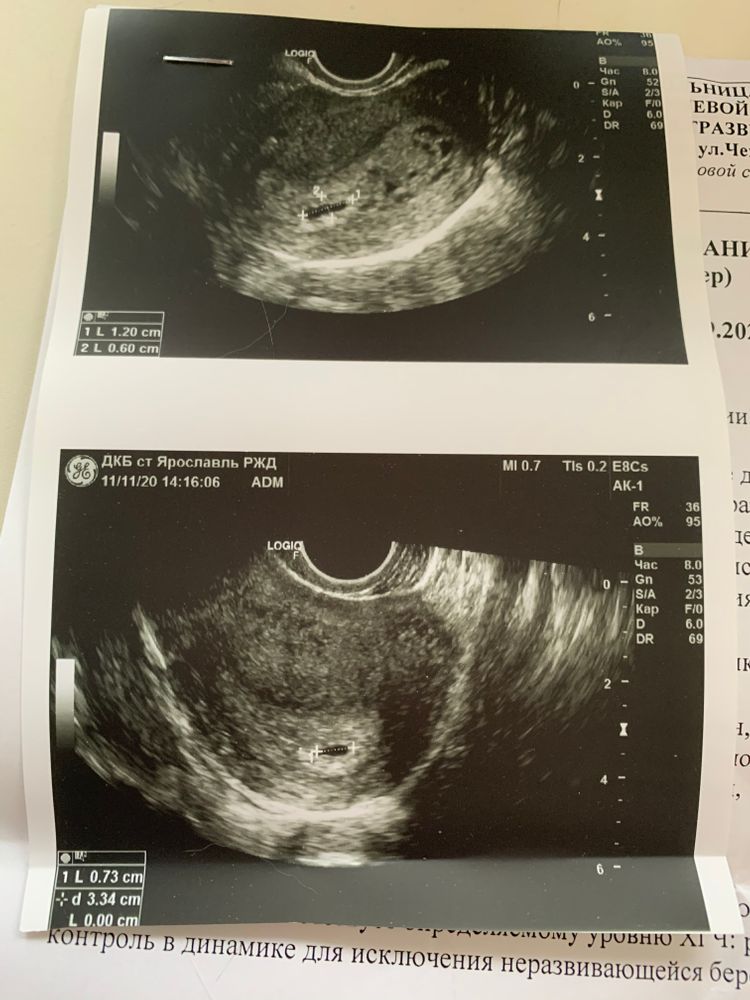

Я уже ничего не понимаю! Вчера была на узи, долго объяснять, можете посмотреть мой предыдущий пост. Так вот, врач узи посоветовала мне сходить в другую лабу, типа большое хгч, а на узи нихера. Сдала я сегодня, там результат через час готов. Я в шоке! 75!!! А результат позавчерашний - 2400!!! При чем до этого сдавала в динамике в одной лабе и все росло нормально. Как такое возможно за два дня? Это зб? Сделала тест на дневную мочу - полоска сразу проявилась яркая! Позвонила в лабу, сказали ошибки быть не может. Сегодня иду к врачу. Я просто с ума схожу. Блин, в дневник не добавляется пред. Запись. Прикрепляю узи вчерашнее. Там мне сказали. что при таком хгч должно быть видно больше и сказали наблюдать.

На узи, кстати, пя видно. А хгч 2400 это не много, поэтому и пя такое еще маленькое.

На узи у вас нашли ПЯ.

А ХГЧ пересдайте

Elena Monakova, до вчерашнего дня все было ок, рос хгч. Но вчера сделала узи и мне сказали, что уровень хгч не совпадает с тем что видят на узи. Боюсь что это зб теперь